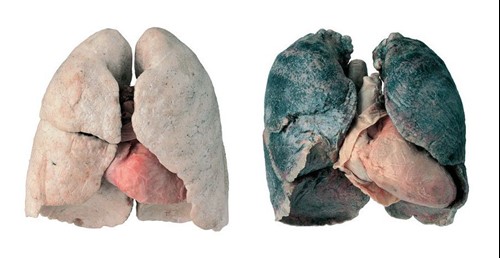

Bij BODY WORLDS staat een stel geplastineerde rokerslongen. Ze zijn zwart en verschrompeld. De gevolgen van roken worden hier pijnlijk zichtbaar. Je hoeft geen dokter te zijn om te zien dat deze longen ongezond zijn. Deze zwarte kleur en longschade worden veroorzaakt door giftige stoffen, zoals teer, die rokers bij elke sigaret binnenkrijgen. Durf je de confrontatie aan? Haal je ticket voor BODY WORLDS hier.

Rokers hoesten vaak en zijn eerder buiten adem. Ondanks het hoesten, krijg je als roker niet alle stoffen weer uit je longen. Daardoor ontstaat na verloop van tijd longemfyseem, waarbij de luchtzakjes in je longen afsterven. Vandaar dat je eerder buiten adem bent: je hebt simpelweg minder long over. Andere gevolgen van roken voor de longen zijn een verhoogde kans op bronchitis (ontsteking in de longen) en longkanker. Tot slot is een roker vaker verkouden en heeft hij vaker griep en ontstekingen aan de luchtwegen.